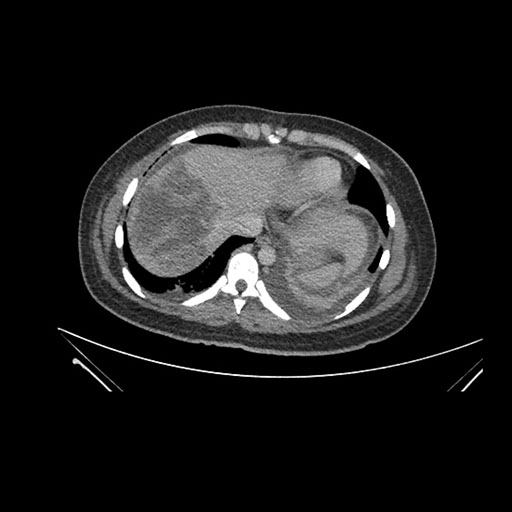

Imaging Analysis

Look through the patient's CT scan to identify any areas of concern for the necessary procedure.

Axial Venous